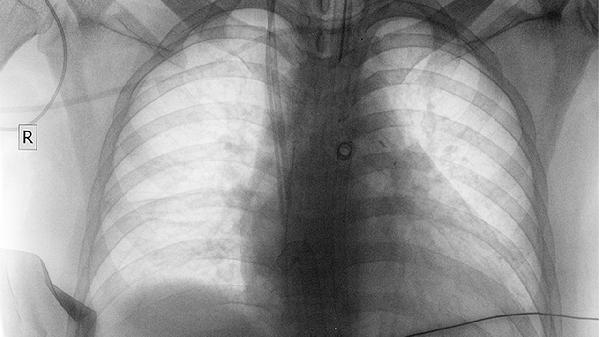

85岁老人肺癌早期可通过手术、放疗、化疗等方式治疗。肺癌可能与长期吸烟、环境污染、遗传等因素有关,通常表现为咳嗽、胸痛、呼吸困难等症状。

1、手术治疗:对于早期肺癌患者,手术是首选治疗方法。常见手术方式包括肺叶切除术和楔形切除术。肺叶切除术适用于肿瘤局限于一个肺叶的情况,楔形切除术适用于肿瘤较小的患者。手术可以彻底切除肿瘤,降低复发风险。

2、放疗治疗:放疗适用于不适合手术或术后辅助治疗的患者。放疗通过高能射线杀死癌细胞,减少肿瘤体积。放疗可以单独使用或与化疗联合使用,提高治疗效果。

3、化疗治疗:化疗通过药物杀死癌细胞,适用于晚期或转移性肺癌患者。常用化疗药物包括顺铂、卡铂、紫杉醇等。化疗可以单独使用或与放疗联合使用,延长患者生存期。